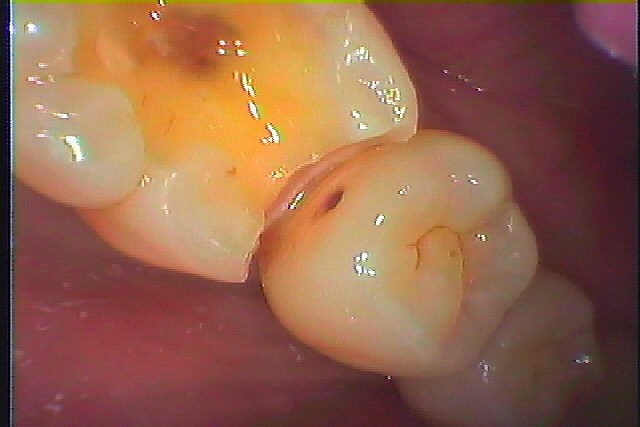

下顎の6番 見えるところの銀歯は外してセラミックへやり変えていきたい|お知らせ |広島市安佐南区の歯科医院 下顎の6番 見えるところの銀歯は外してセラミックへやり変えていきたい トップ お知らせ・ブログ お知らせ 下顎の6番 見えるところの銀歯は外してセラミックへやり変えていきたい 下顎の6番 見えるところの銀歯は外してセラミックへやり変えていきたい この銀歯をはずしていきます 外すとこんな感じになっていました 下には虫歯が存在していました 遠心部も虫歯で伸ばしました 7番は大丈夫でした 近心部も虫歯で伸ばしました 5番の方まで虫歯になっていました 虫歯を除去しCR樹脂にて修復しています 6番はCR樹脂にて覆罩を行っています セレックセラミックが綺麗に入りました 喜んでいただきました Web診療予約 初めての方へ 選ばれ続ける理由 院内設備について 歯が痛いしみる一般歯科 歯がぐらぐらする歯周病 健康な歯を保ちたい予防歯科 子供の虫歯予防をしたい小児歯科 銀歯をセラミックに審美歯科 白い歯を目指しませんか?ホワイトニング 矯正専門医がいるので安心矯正歯科 抜けた歯を補いたいインプラント・入れ歯 医院案内 スタッフ紹介 メリィハウス歯科クリニックオフィシャルホームページ ラベンダー歯科クリニックオフィシャルホームページ お知らせ・ブログ ホーム 診療科目 一般歯科 歯周病治療 予防治療 小児歯科 審美治療 ホワイトニング 矯正歯科 入れ歯・インプラント マウスピース矯正 初めての方へ 院長・スタッフ 設備紹介 医院案内・アクセス メニューを閉じる